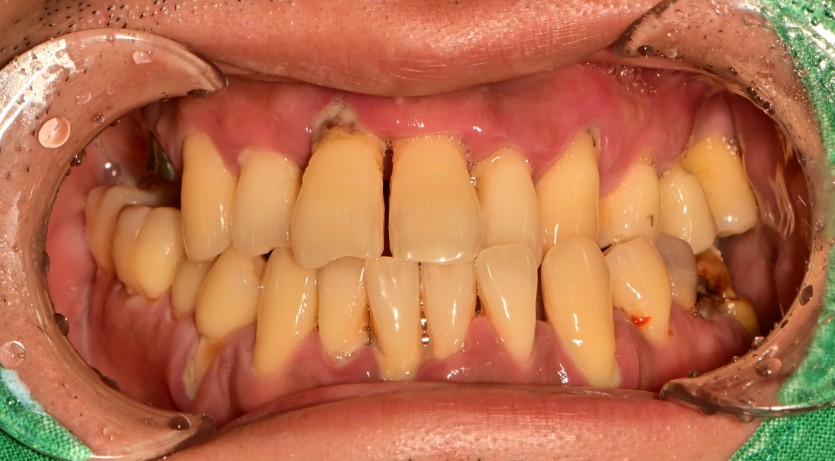

전체 임플란트 증례입니다.

18개의 임플란트로 완성하였습니다.